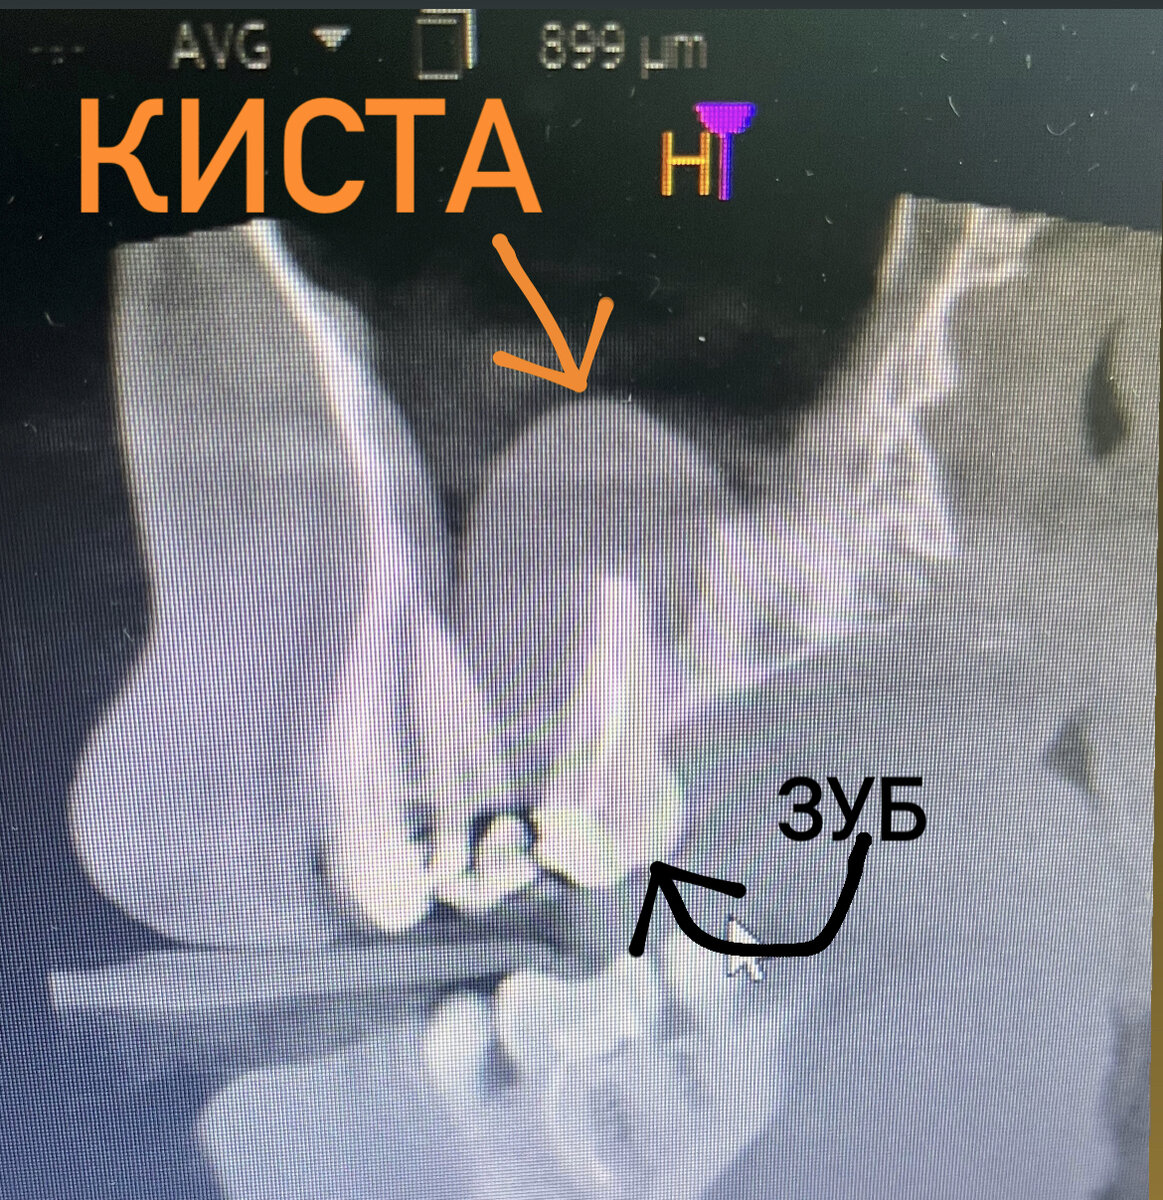

Личный архив ЛОР-врача Анны Леончик

Также в формировании кист играют роль хронические воспалительные процессы зубов (пульпиты, периодонтиты).

Связь кисты пазухи носа и зуба